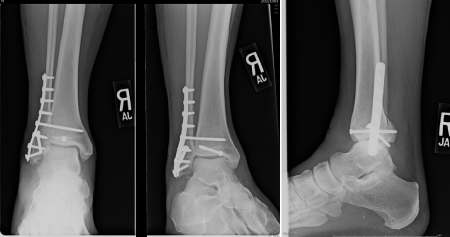

Figure 2 AP, Mortise & Lateral of initial post-reduction of right Bosworth fracture-dislocation.